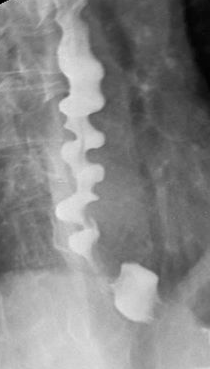

Manometry: Intermittent peristalsis,multiple simultaneous contractions Esophagram: "Corkscrew" pattern

This patient with intermittent non-cardiac chest pain and dysphagia has typical symptoms of diffuse esophageal spasm (DES). DES is characterized byuncoordinated, simultaneous contractions of the esophageal body, likely related to impaired inhibitory innervation in the esophagus. DES is frequently seen in association with emotional factors and functional gastrointestinal disorders. Symptoms often resemble those in achalasia (impaired esophageal motility with incomplete relaxation at the lower esophageal sphincter) and nutcracker esophagus (excessive tone at the lower esophageal sphincter).

The diagnosis of DES is challenging due to the episodic nature of clinical features. Esophageal manometry reveals intermittent peristalsis and multiple simultaneous contractions of the middle and lower esophagus. The lower esophageal sphincter usually shows normal relaxation. Esophagram may show nonperistaltic contractions producing a "corkscrew esophagus" pattern, although this is neither sensitive nor specific. Endoscopy is usually normal. First-line treatment includes calcium channel blockers (eg, diltiazem), which relieve pain and reduce dysphagia.